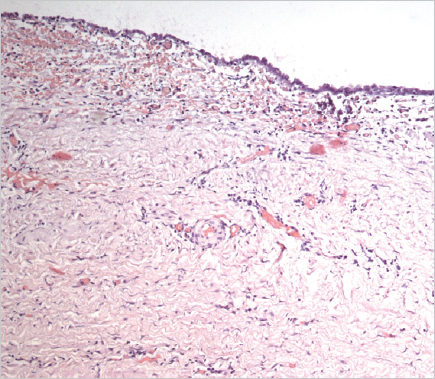

Histological examination of the removed paraurethral cyst was performed (Fig. 6–8).

Fig. 7.The wall of the paraurethral cyst, surgical material. Hematoxylin-eosin staining, ×100. Epithelium with signs of dystrophia and minimal desquamation are represented

Рис. 7.Стенка парауретральной кисты, операционный материал. Окраска гематоксилином и эозином, ×100. Эпителий с признаками дистрофии и минимальной десквамации

Fig. 8.The wall of the paraurethral cyst, surgical material. Hematoxylin-eosin staining, ×100. Foci of epithelial lining atrophy are determined

Рис. 8.Стенка парауретральной кисты, операционный материал. Окраска гематоксилином и эозином, ×100. Определяются очаги атрофии эпителиальной выстилки